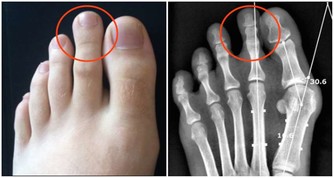

水毒陰毒中最嚴重的就是水毒,一般由腎功能衰弱引起。40歲以上的人應該注意,如果早上起來下眼皮、腳踝浮腫,很有可能就是水濁。想要驅逐水毒,首先要看醫生,檢查腎臟和心臟有無疾病,如果水毒是因腎功能不好導致的,可以服用金匱腎氣丸,通過溫腎來調動機體的氣化能力;如果腎臟和心臟都沒有病,那說明氣血運行不好,需要多運動,飲食上可多吃一些除水濕的絲瓜、冬瓜等。